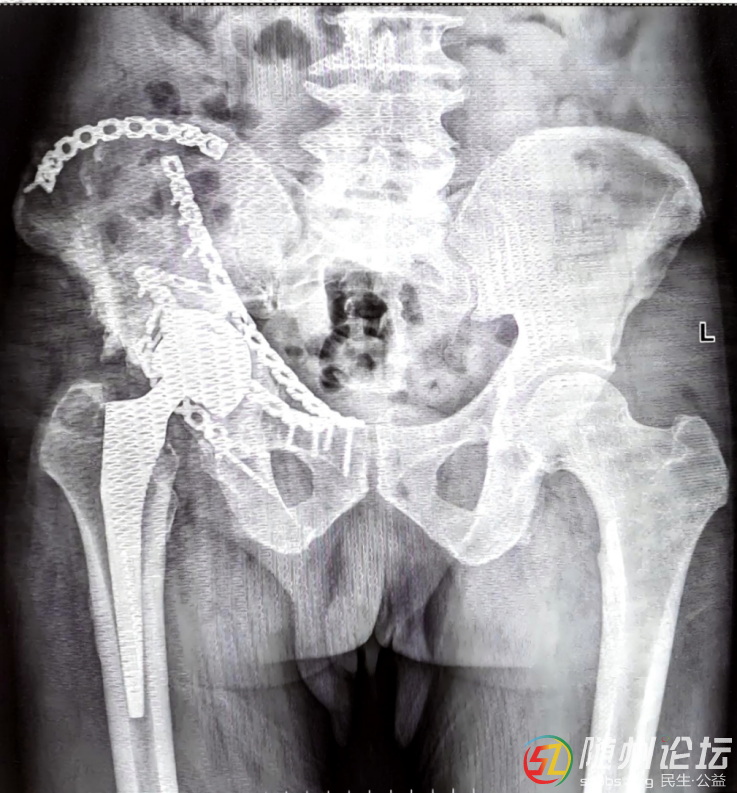

63歲的姜老先生,2019年因車禍導(dǎo)致骨盆和肋骨骨折在外院手術(shù),術(shù)后恢復(fù)良好。2021年他又因股骨頭壞死接受髖關(guān)節(jié)置換術(shù),術(shù)后恢復(fù)較為順利。

2025年2月,原骨盆手術(shù)部位破潰流膿,雖經(jīng)多家醫(yī)院抗生素和傷口換藥治療,效果不佳。2025年3月,慕名而來的姜先生,在隨州市中心醫(yī)院骨科門診找到了主任蔡平原,蔡平原仔細(xì)查看病情后,診斷為“右髂骨骨髓炎”,并立即安排其入院治療。

經(jīng)綜合評(píng)估,團(tuán)隊(duì)為他進(jìn)行了第一次手術(shù),取出了原先植入的鋼板,徹底清理了受感染的骨頭,并填入了一種能持續(xù)釋放藥物的特殊材料來控制感染。這次手術(shù)后沒有立即縫合傷口,而是安裝了專門的沖洗和引流裝置。在接下來的近兩個(gè)月時(shí)間內(nèi),姜老先生又先后接受了兩次清創(chuàng)手術(shù)。最終,傷口大部分愈合,體內(nèi)仍保留著用于控制感染的特殊材料。

同年9月,姜老先生回來復(fù)查。與半年前相比,他一進(jìn)病房就能主動(dòng)和醫(yī)護(hù)人員打招呼、聊天,精神狀態(tài)好了很多。他表示傷口已不再流膿。蔡平原評(píng)估后,決定再次為他進(jìn)行手術(shù),取出了之前的特殊材料,并對(duì)傷口周邊組織進(jìn)行了修整,最后縫合了傷口。